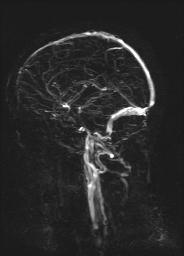

Schädel Perfusion |

vessels_head_MIP_SAG |